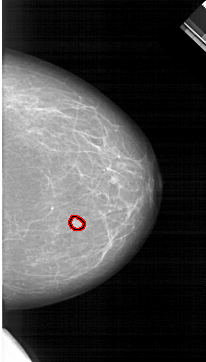

FILE: A_1264_1.RIGHT_MLO.OVERLAY

TOTAL_ABNORMALITIES 1

ABNORMALITY 1

LESION_TYPE MASS SHAPE OVAL MARGINS CIRCUMSCRIBED

ASSESSMENT 3

SUBTLETY 4

PATHOLOGY BENIGN

TOTAL_OUTLINES 1

BOUNDARY

RIGHT_MLO LINES 6706 PIXELS_PER_LINE 3631 BITS_PER_PIXEL 12 RESOLUTION 43.5 OVERLAY